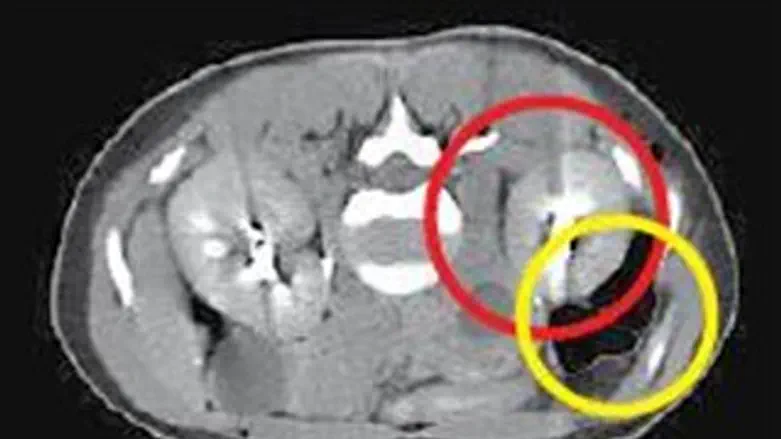

העובר לא היה ברחם שלה וגם לא בחצוצרות, מקום שבו בדרך כלל משתרשים הריונות מחוץ לרחם. בבדיקת האולטרסאונד נמצא שההריון השתרש בין הכליה לבין כלי דם גדול שמוביל אליה. מדובר בדיווח השני בעולם על מקרה שכזה.

"הרופא שליווה את ההריון בקפריסין יצר איתנו קשר והמלצנו לו להטיס את האישה אלינו," אמר פרופ' נרי לאופר, מנהל המערך למיילדות ולגינקולוגיה בבית החולים הדסה, "הריון כזה עלול לסכן את חייה של האישה באופן מיידי. השליה של העובר חודרת לתוך כלי הדם הגדול ועלול היה להיווצר מצב שאבי העורקים של אותה אישה היה מתפוצץ בחלל הבטן וגורם למותה." בהדסה התגייסו להטיס את האישה לארץ באמצעות "אמבולנס מעופף" - מסוק עם ציוד רפואי וליווי רפואי שנמצא בבית החולים הירושלמי. לדברי פרופ' לאופר, אי אפשר היה להמשיך את ההריון הזה בשל הסיכון הרב לחיי האישה ולכן הוחלט לבצע הפסקת הריון: "לאחר ביצוע הפסקת ההריון ראינו דם בכמות גדולה שהצטבר מתחת לכליה. קראנו לכירורגים מומחים לכלי דם משום שהיה חשש שהאישה תאבד את הכליה. למרות הזרקת חומר שחוסם את כלי הדם האישה המשיכה לדמם והוכנסה לחדר ניתוח. קיבצנו כמות גדולה של רופאים מומחים, רנטגנולוגים, כירורגים כלליים וכירורגים של כלי דם ובמהלך הפעולה - שנמשכה 48 שעות ברצף - התברר לנו שההריון כבר חדר לכלי דם גדולים." בסופו של דבר הצליחו המנתחים לסגור את כלי הדם מעל ומתחת למקום שבו השתרשה השליה והתפתח ההריון, ולהציל את חייה של האישה בלי לפגוע בכליה שלה. במהלך הניתוח התבררה עובדה מעניינת נוספת - העובר ניקב את ציפוי הבטן ולמעשה חדר לאחוריו. לדברי פרופ' לאופר, "זהו מקרה מאוד נדיר. השכיחות של הריון מחוץ לרחם נעה בין חצי אחוז לאחוז בודד, אך בהריונות שהושגו בהפריה חוץ גופית היא גבוהה יותר ועומדת על 5-2 אחוזים. רוב ההריונות שמחוץ לרחם נמצאים בחצוצרה ונדיר ביותר שהריון יימצא בחלל הבטן. לצערי, לא היה אפשרי במקרה הזה להציל את ההריון, אך אני שמח שאפשר היה להציל את האישה."